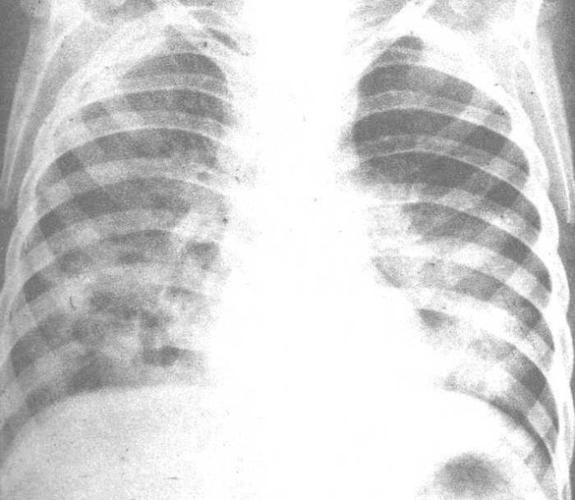

间质性肺炎x线图片,间质性肺炎x线

1x线胸片检查,ct扫描一般情况通过x线胸片检查,间质性肺炎晚期较容易

间质性肺炎x线

间质性肺炎胸片

间质性肺炎图片

间质性肺炎影像学